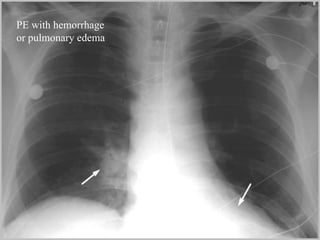

Pulmonary embolism (PE) is a common and potentially fatal condition where blood clots block arteries in the lungs. An estimated 5 million venous thromboses occur annually worldwide, with 10-30% of cases resulting in PE. Risk factors include immobilization, surgery, cancer, and estrogen use. Diagnosis involves assessing clinical probability based on symptoms and risk factors, followed by tests like D-dimer, chest imaging, ultrasound, V/Q scan, CT, or angiogram. Treatment aims to prevent further clotting with anticoagulants like heparin and warfarin, provide supportive care, and in some severe cases utilize thrombolysis or embolectomy.